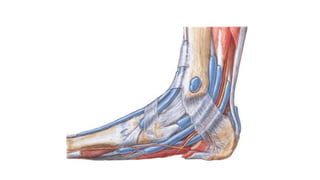

REGION PIE

Superficie del pie